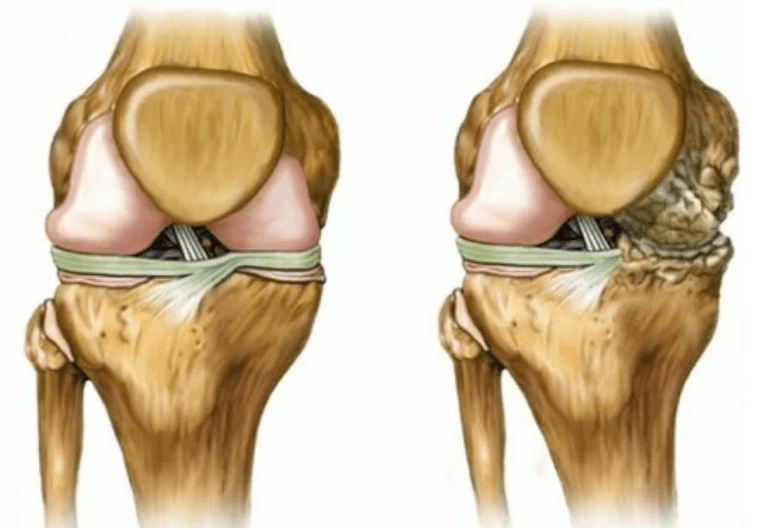

The arthrosis of the joint develops for a long time, initially affects only the cartilage IALINA, then spreads to the bones, involves the synovial shell, the muscles and the entire capsule of the joint.In the first or early phase of arthrosis, the lesion manifests itself slightly: small pains after hard work, swelling, redness of the skin.Due to the ignorance of uncomfortable sensations, the articulation is deformed, inflamed, brings serious pain, their peak falls in the morning.The disease is characterized by the disappearance of pain after the development of the joint.If not treated, a person completely loses the mobility of the joint.

- 1 degree.Morphological disorders have already started, but are not yet evident.The pathology mainly affects the condition of the synovial fluid, which worsens the cartilage tissues with nutritional components, reducing the strength of the cartilage.The load on the joints causes inflammation and pain.

- Phase 2The pains acquire a more pronounced character, intensified after a long rest, they are eliminated by a small physical labor.The pain is accompanied by inflammation.The muscles are elongated, which leads to motor functions with weak or medium disabilities.

- 3 degrees.Often there are pains, it is difficult to move the limb due to changes in the joint.The lesions are extended, they become evident to the naked appearance.The deformation of the joint site occurs, the affected area swells and becomes red.The axis of the limb is disturbed, which leads to the complexity of the movement.Pathological changes cause the shortening of ligaments.Subbules and contractures appear.The adjacent muscles are abbreviated or elongated, from which the contractile function is weakened.